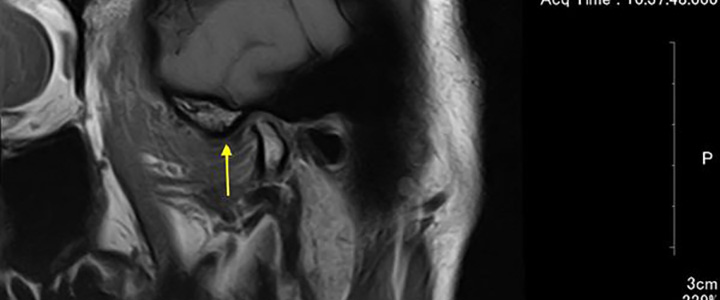

これは顎関節のMRI画像です。歯科医はこれを見て、この患者さんのお口の中を想像出来なくてはならないと考えています。 顎関節は身体の関節の一部なので、構造的…

名取歯科医院で治療を受けていただく場合には、MRI撮影が必須になります。 肘や膝に問題があった場合、整形外科では必ずにMRI撮影をするはずです。なぜならば…

顎関節の軟骨部分を関節円板と言いますが、これが咬み合わせに大きな影響を及ぼしています。 こちらの画像のように関節円板が正常な位置にあれば何にも問題は起こりませ…